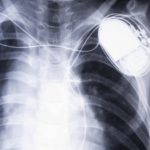

The heart rate of healthy adults should be between 60 to 80 beats per minute. If a person’s heartbeat is slower than that, the disorder is called bradycardia.

There are many reasons why a person’s heartbeat may run fast, or slow. For example, adults who regularly exercise will have a slower resting heartbeat. Additionally, seniors are typically prone to a slower heartbeat as aging causes the heart muscles to weaken. Although these reasons are harmless, bradycardia could also signify a more serious condition. If the heart cannot pump a sufficient amount of blood, symptoms and complications may arise. Continue reading…